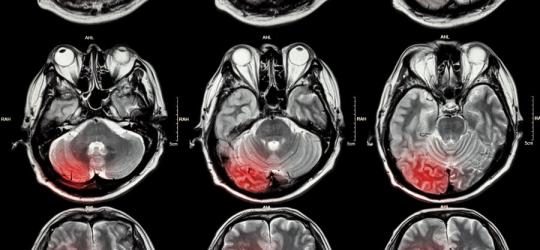

- Neurologia